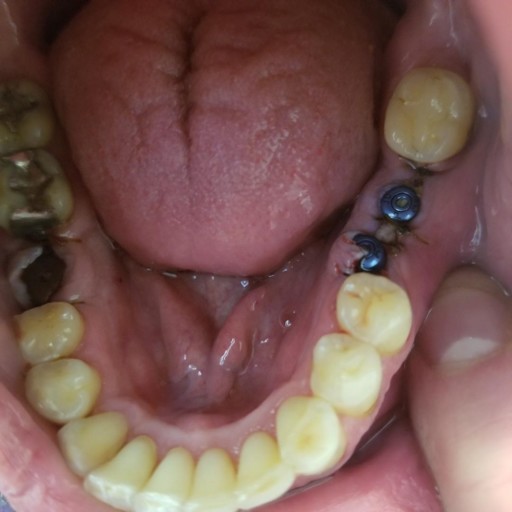

My implant cover screw came out

My dental implant cover screw came out for 2 days before I could have it replaced(the implant was placed 3 mos ago and I was just cleared to get my tooth). It was quite painful when replacing, and the tissue had started growing over already, but my surgeon said the implant was solid as a rock. Within a few hours I had more pain and swelling. The next day even more pain and swelling- couldn’t close my lips all the way… the pain is throbbing and severe, even after taking motrin around the clock and ice compresses. They didn’t clean my mouth or the implant hole out before they replaced the screw… I asked about it and was told it wasn’t necessary. I don't know if it mattered, but now I think its infected, and It’s the weekend of course, so the on call dentist put me on amoxicillin which I have been on for 24hrs now with no change in the pain or swelling yet. Will this get better soon, or may I need IV antibiotics? Please help, I am so miserable!

I had 3 implants done yesterday, with 2 that were next to each other (see picture). One is not aligned. I am also doing ortho care and went in today to have a new retainer fitted. The dentist said he did not want to do new impressions due to the...